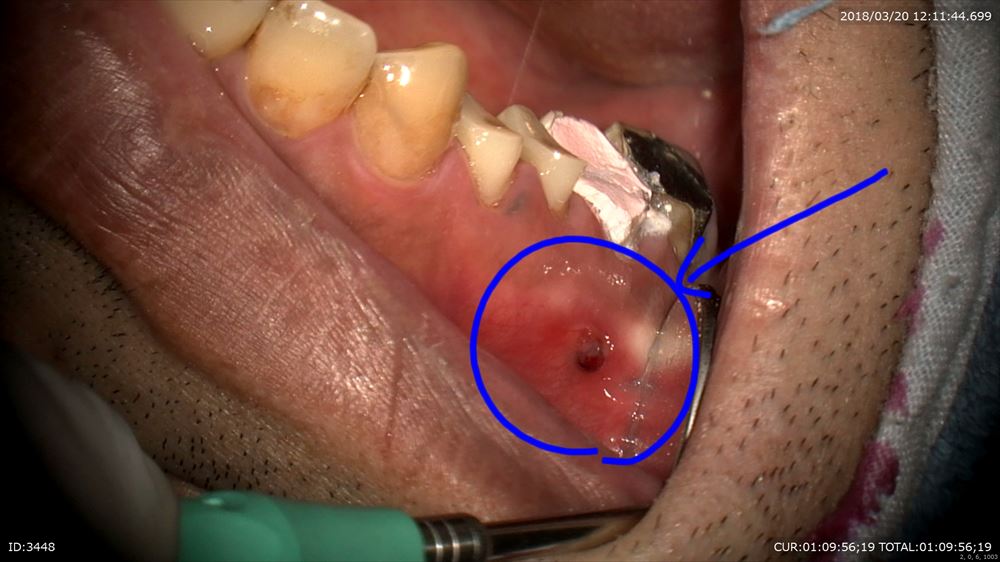

では今日もマイクロスコープを使用した重症の虫歯のケースを御紹介。

精密根管治療

虫歯菌が骨まで移動し歯茎から出てきてしまっている状況です。

やはり治療されていない根管1つ目発見

ここだ。

ここでした。マイクロスコープを使用しなければ私には見えませんでした。